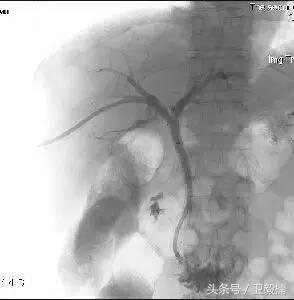

一、全身各部位血管造影;

一、血管介入放射学

亦称介入性血管造影学(Interventional angiography),是指在诊断性血管造影的同时,自导管向血管管腔内注射药物或某些物质或施行某种措施,以达治疗目的。常用血管介入技术有三种。